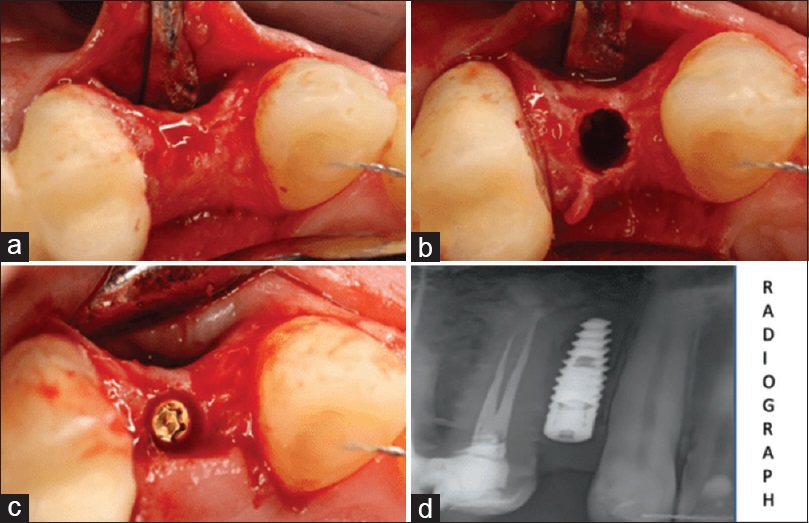

Sursa foto: PMC11660531

Un element distinctiv al osteodensificării este modul în care irigarea și particulele osoase autogene contribuie la formarea unei unde hidraulice în interiorul osteotomiei. Această undă hidraulică apare în momentul în care freza ajunge în apropierea planșeului sinusal și transmite o presiune progresivă către membrana Schneider, fără contact direct sau impact mecanic. În acest fel, membrana este separată gradual de patul osos și ridicată într-un mod controlat, concomitent cu depunerea particulelor osoase autogene submembranare.

Aplicată în procedura de lifting sinusal crestal, osteodensificarea modifică fundamental mecanismul ridicării membranei sinusale. Spre deosebire de tehnicile clasice cu osteotoame, unde elevarea este obținută prin impact sau fracturarea controlată a planșeului sinusal, osteodensificarea permite o ridicare progresivă, dependentă de presiunea hidraulică și de proprietățile mecanice ale membranei. Acest mecanism explică interesul crescut pentru utilizarea sa în maxilarul posterior, unde densitatea osoasă redusă și înălțimea osoasă reziduală limitată pot compromite predictibilitatea abordului crestal.